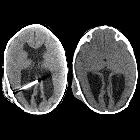

low grade fever and redness and swelling around the VP shunt reservoirAxial CT without contrast of the brain shows a low density fluid collection around the VP shunt reservoir between the skull and the scalp. In the operating room this fluid was found to be pus.The diagnosis was an abscess around the VP shunt reservoir.